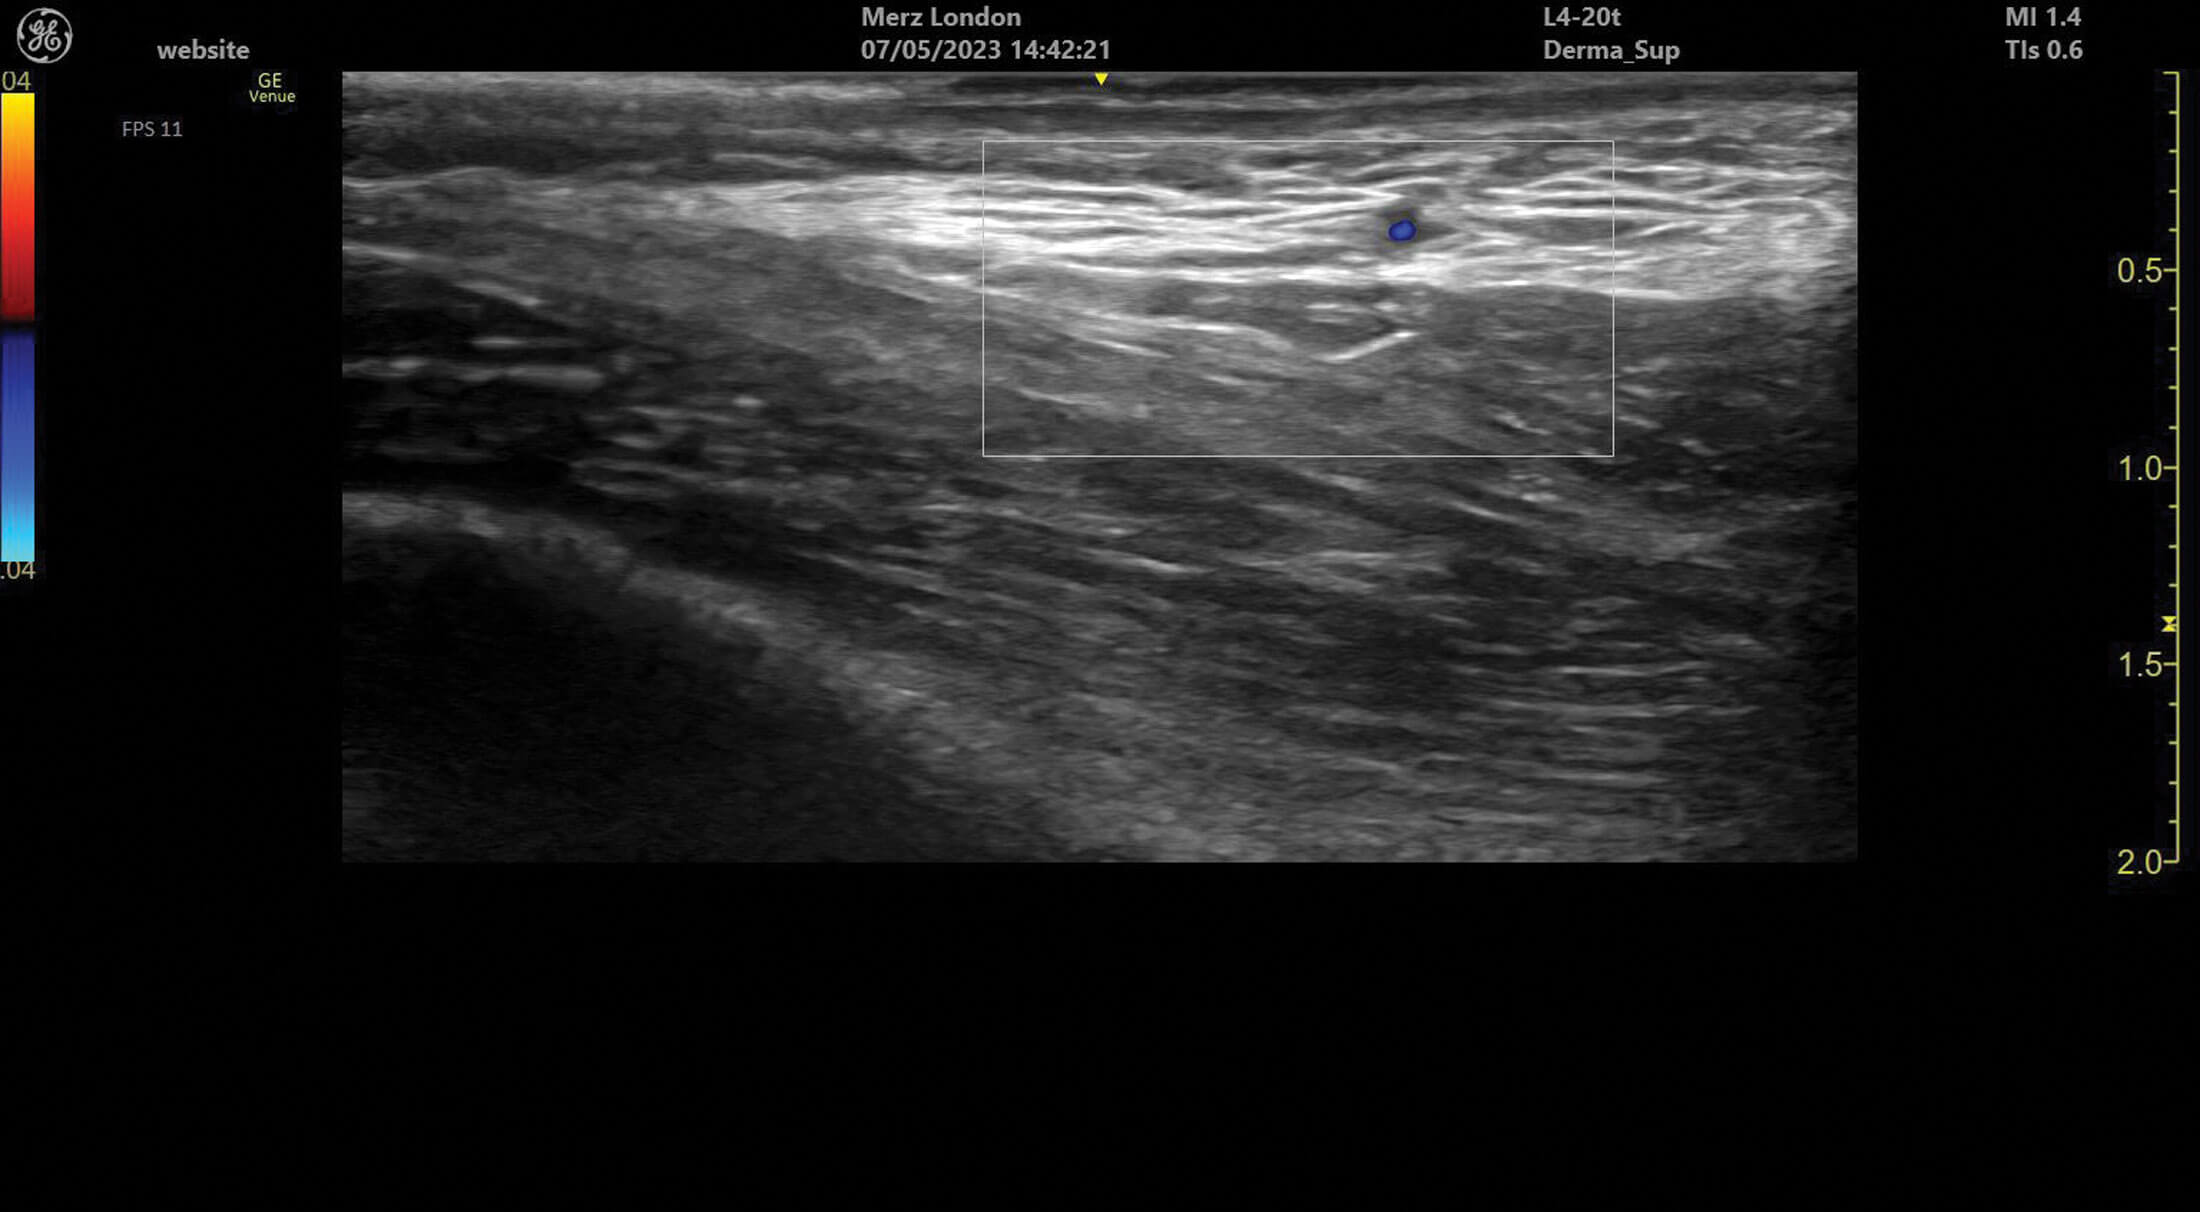

Figure 3: A branch of the superficial temporal artery in superficial tissues of the temple.

Ultrasound doppler can be used to assess blood vessel flow prior to treatments but can also help identify abnormalities in blood supply after filler treatment. Vessels can be identified and tracked in the tissue allowing for the observation of any anatomical variation. Blood vessels always appear as anechoic structures on ultrasound but, when using a colour doppler, flow can be detected either towards (red) or away (blue) from the ultrasound probe [1].

Ultrasound competence can take time to master but previous modality experience results in quicker ease of use [1]. Practice with scanning facial structures and differentiating between soft tissue layers is essential, along with formal training. I would caution against social media education as I find that self-proclaimed experts can misidentify structures on public forums, leading to misdiagnosis and mistreatment. Visualisation training is unfortunately not included with devices and can lead to treatment decisions being taken on poor quality images by unqualified practitioners. Identifying filler and even anatomical structures requires patience and hours of dedicated practice. Vascular mapping is difficult, and the lack of vessel visualisation does not exclude the presence of vascular structures, which can lead to a false sense of reassurance to inexperienced users and should always be used in conjunction with current safety advice, such as minimal bolus volumes and capillary refill assessment before and after treatment [2].